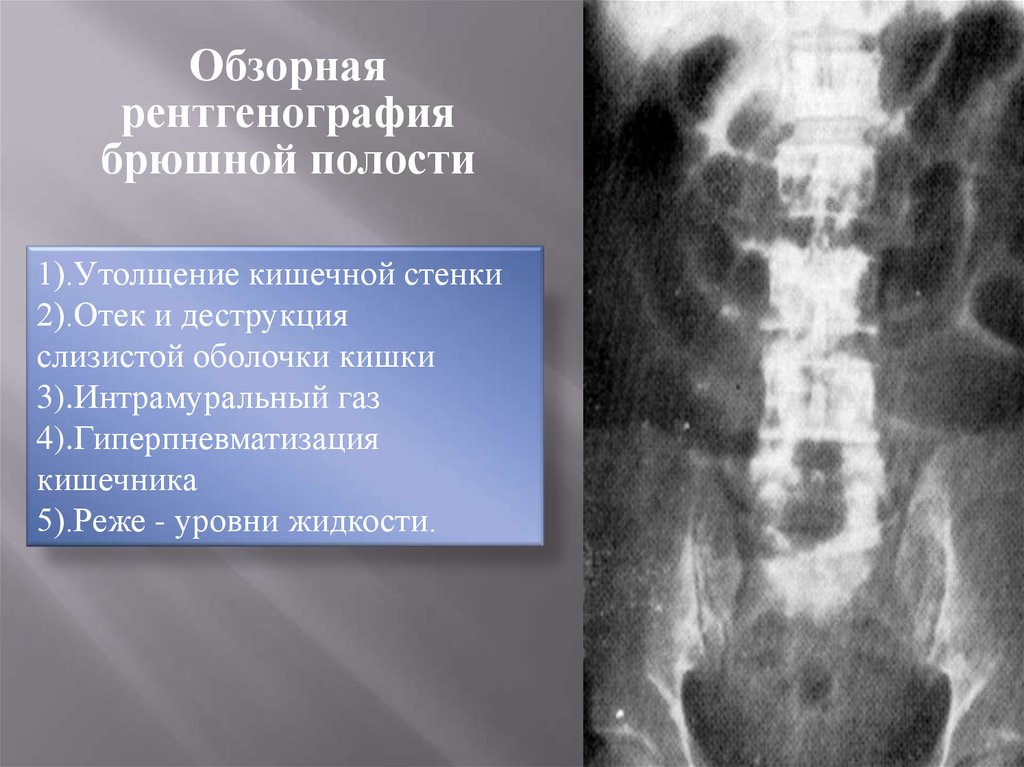

Нормы обзорной рентгенографии брюшной полости